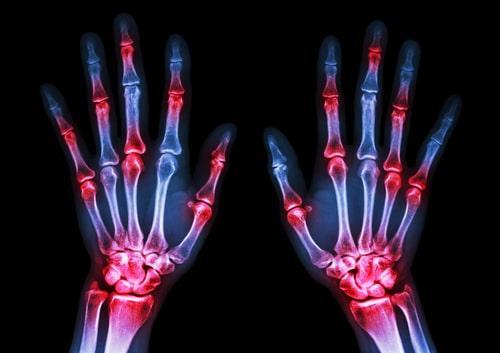

Let's take this recent decision from a federal magistrate judge here in Illinois, Matthew DS v. Saul. In this case, Social Security denied the disability application of a man (the plaintiff) who suffers from “inflammatory arthritis, rheumatoid arthritis, and obesity.” Following a hearing, a Social Security administrative law judge (ALJ) determined these impairments did not qualify the plaintiff for the disability benefits.

- The ALJ said the plaintiff's medical exams showed his “small joints” were “unremarkable,” i.e. not disabling, yet the ALJ also acknowledged the plaintiff had “moderate rheumatoid arthritis with predominant large joint involvement."